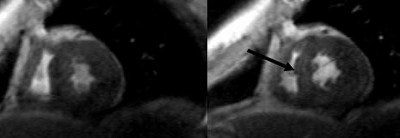

![]() |

| Diastolic (A-C) and systolic (D-F) images in the left ventricular outflow tract view. Images at rest (A and D) and low-dose (B and E) show normal contractility. At high-dose dobutamine (C and F), a stress-induced wall motion abnormality (arrows) can be detected. Image courtesy of Dr. Jörg Barkhausen. |